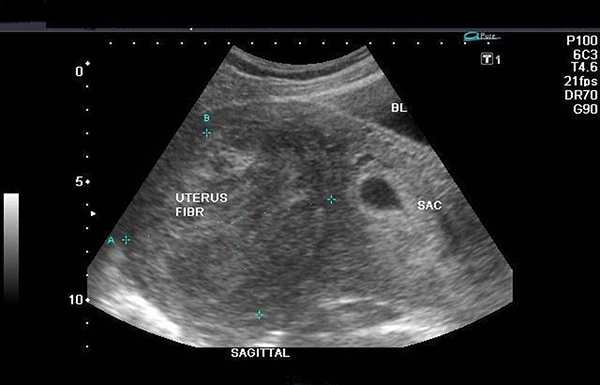

– U xơ tử cung:

Những khối u nhỏ của u xơ sẽ có mặt và phát triển lên từ lớp cơ của tử cung. Từ những hình ảnh thu được từ đầu dò, có thể nhận thấy tình trạng, kích thước hiện tại của các u xơ, từ đó thấy được mức độ nguy hiểm mà chỉ định có nên mổ hay không. Bệnh lý này xuất hiện ở bất kỳ độ tuổi nào, tuy nhiên trong khoảng từ 35 – 50 khả năng mắc bệnh chiếm tỷ lệ cao hơn.

– Hiện tượng mang thai ngoài tử cung:

Sử dụng phương pháp siêu âm này, giúp xác định chính xác vị trí của thai nhi khi phụ nữ mang thai ở tuần thứ 4 hoặc 5 của chu kỳ mang thai sản. Do đó, qua việc quan sát những hình ảnh thu được bác sĩ có thể thấy được trường hợp sản phụ mang thai ngoài tử cung. Điều này sẽ giúp phát hiện và có biện pháp xử lý, ngăn chặn kẹp thờ để tránh những điều không may xảy ra như: vỡ ống dẫn trứng, nhiễm trùng ổ bụng,…